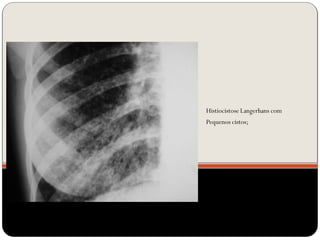

Histiocistose Langerhans com

Pequenos cistos;

cistos

1.Linfangioleiomi

omatose

2.PIL

3. Histiocistose de

langerhans

 Cistos (LAM, Histiocistose de Langerhans, PIL)